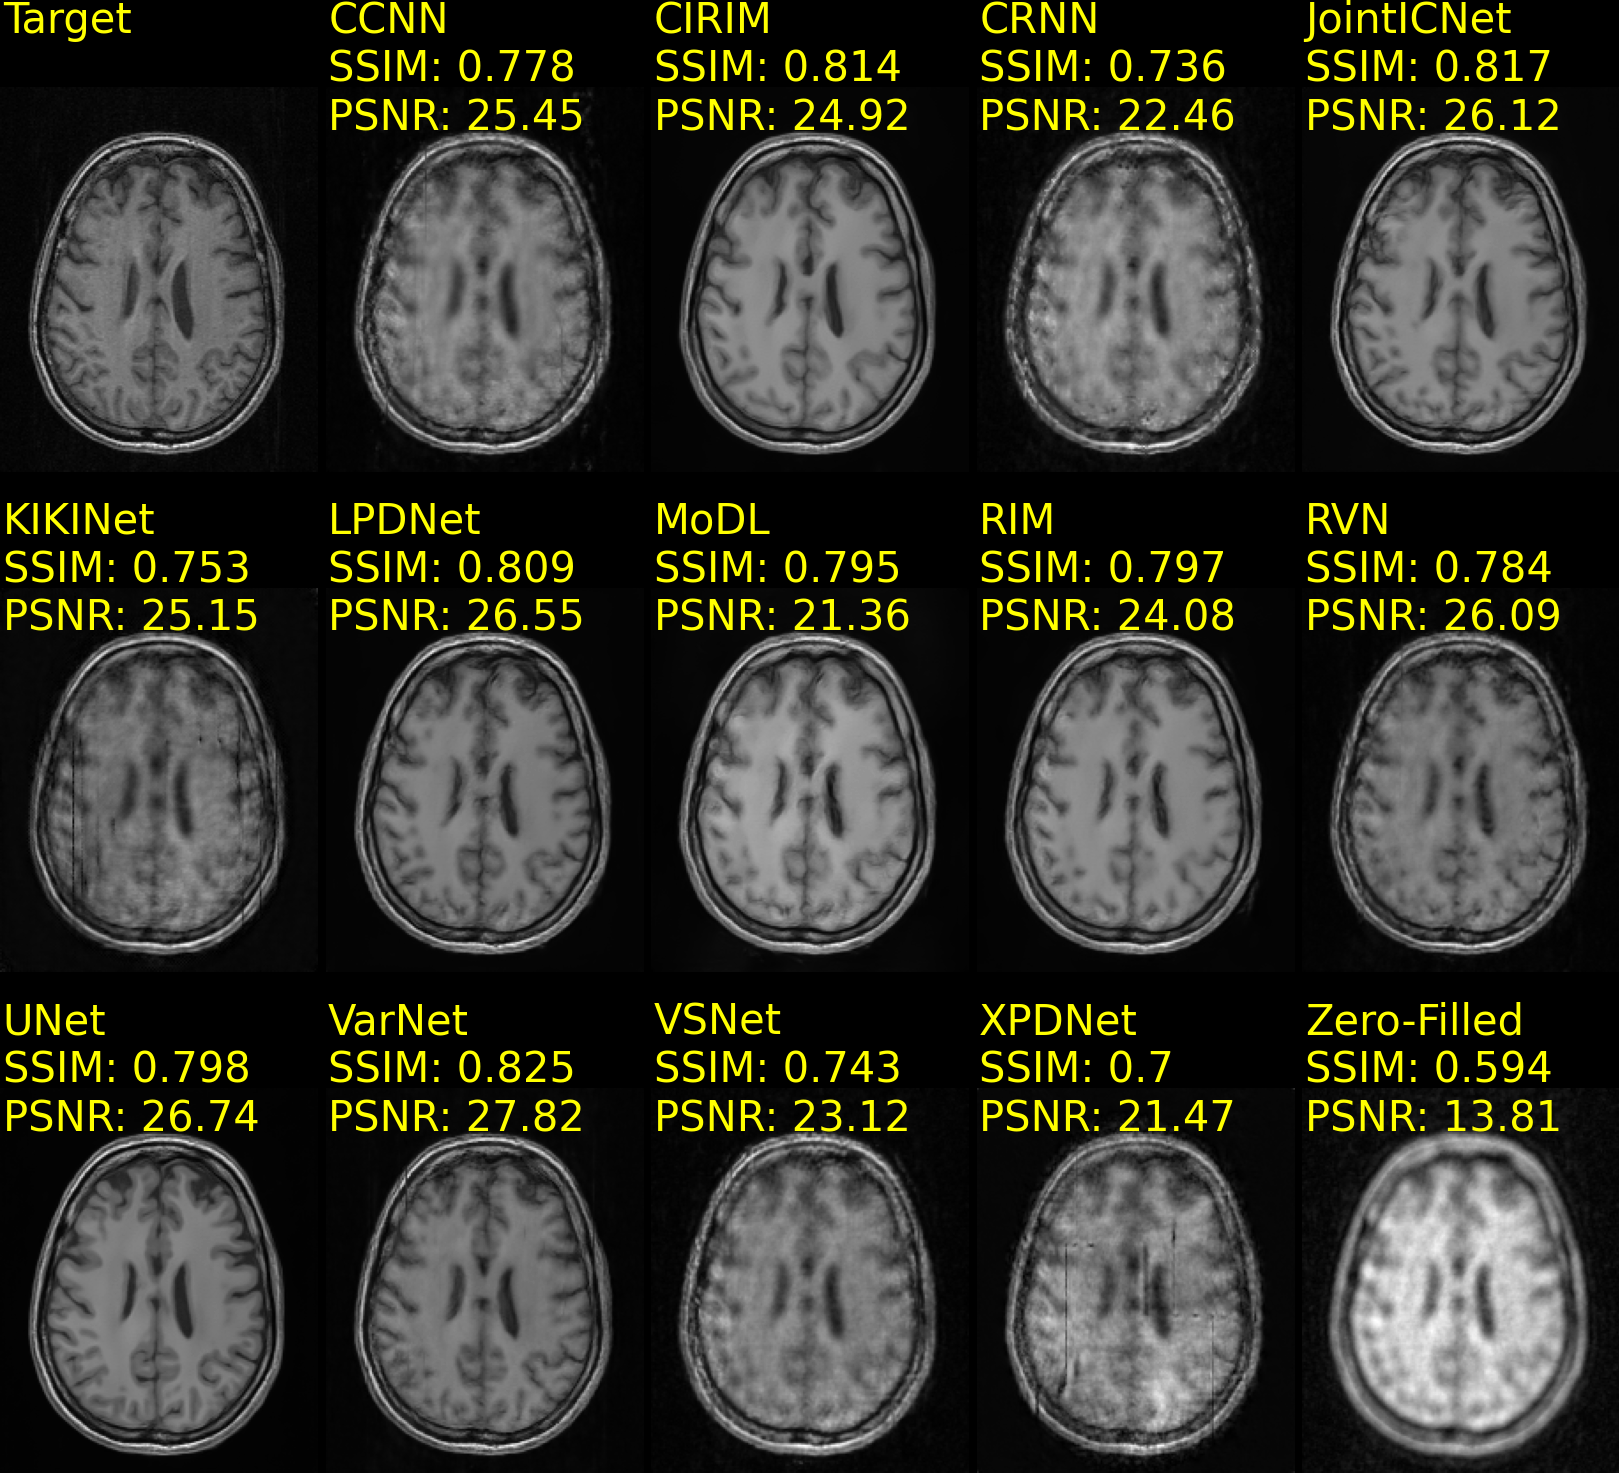

Table 2 presents the reconstruction task performance of models trained on the CC359 and fastMRIBrains datasets. The Variational Network (VarNet) achieved the highest SSIM and PSNR scores for 5x acceleration and the highest PSNR score for 10x acceleration on the CC359 dataset. The Joint Deep Model-Based MR Image and Coil Sensitivity Reconstruction Network (JointICNet) scored the highest SSIM for 10x acceleration on the CC359 dataset. In contrast, on the fastMRIBrains dataset, the Recurrent Variational Network (RVN) scored the highest SSIM and PSNR scores for 4x acceleration and the VarNet for 8x acceleration. The Cascades of Independently Recurrent Inference Machines (CIRIM) yielded the highest SSIM and PSNR scores on the StanfordKnee dataset for 12x acceleration, as presented in Table 3. Conversely, on the same dataset, the Convolutional Recurrent Neural Network (CRNN) was excluded from the analysis due to unstable gradient computation, although trained across a wide range of learning rates (104superscript10410^{-4} to 109superscript10910^{-9}).

Example reconstructions of brain data are shown in Fig. 5(a) and Fig. 5(b), from the CC359 dataset, and Fig. 6(a) and Fig. 6(b), from the fastMRIBrain dataset. Figure 7 shows example reconstructions of knee data from the StanfordKnee dataset.

Figure 5: Reconstructions of 12-coil T1-weighted data from the CC359 dataset, undersampled with a Poisson disc distribution 2D sampling pattern for 5x (Fig. 5(a)) and 10x (Fig. 5(b)) acceleration. The top row-first column shows the ground truth (Target) image. SSIM and PSNR scores are reported for each method and computed against the Target image. Methods are sorted alphabetically.

Refer to caption

(a) fastMRIBrains 14-coil data - 4x acceleration

(b) fastMRIBrains 14-coil data - 8x acceleration

Figure 6: Reconstructions of 14-coil T2-weighted data from the fastMRI Brains dataset, undersampled with an Equispaced 1D sampling pattern for 4x (Fig. 6(a)) and 8x (Fig. 6(b)) acceleration. The top row-first column shows the ground truth (Target) image. SSIM and PSNR scores are reported for each method and computed against the Target image. Methods are sorted alphabetically.